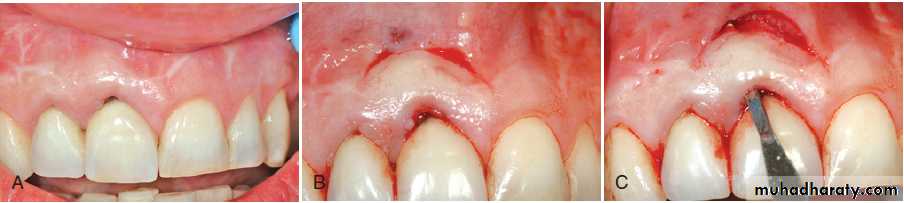

Cell Therapy (Autologous fibroblast)(A) Preoperative view of the open interproximal space. (B) Four months after three injections into the papilla with the patient’s own expanded and concentrated fibroblasts, note the improved papillary form. Green horizontal lines are used for image analysis.